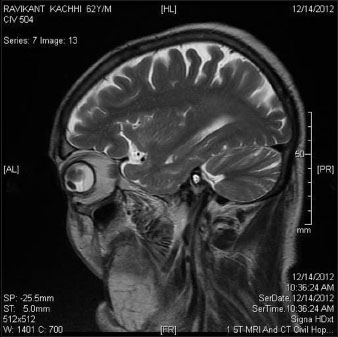

A 62-year-old male diagnosed with carcinoma of the left buccal mucosa in September 2012. He was operated upon (wide local excision of left buccal mucosa with left hemimandibulectomy and modified neck dissection type II) in September 2012. Histopathology report suggested squamous cell carcinoma of size 2.5 cm × 2.0 cm × 1.7 cm. All 31 lymph nodes dissected from left level I to V were free (0/31) of metastasis. No perineural or lymphovascular invasion was seen. Overlying skin was free. Depth of invasion was 0.7 cm. All the margins and cut end of bone were free. It was pathological stage pT2N0Mx. The metastatic workup at the time of surgery was negative for any distant metastasis. The patient was advised adjuvant radiotherapy (60 Gray in 30 fractions) from October 20, 2012 on a 6 MV linear accelerator with a two field wedge plan (Antero Posterior and Lateral field). During treatment (after 28 Gray/14 fractions), the patient presented with painless, gradually progressive diminution of vision of the left eye. A thorough ophthalmological examination was done which included slit lamp examination, ultrasonography (USG) of eyes, and magnetic resonance imaging (MRI) of both eyes and brain. Biopsy was not possible from the choroidal mass. The USG scan [Figure 1] revealed choroidal lesion suggestive of secondaries in the left eye. MRI brain and both eyes [Figure 2] and [Figure 3] showed the presence of altered signal intensity in the posterior chamber of the left eye which was hyperintense in T1-weighted sequence and hypointense on T2-weighted sequence. A solitary deposit in the left choroid involving 80% of the globe with secondary retinal detachment was seen. There was no other choroidal or brain metastasis. Positron emission tomography-computed tomography (PET-CT) evaluation showed metastatic disease in the left choroid, with no other involved site elsewhere in the body.

| Figure. 2 Magnetic resonance imaging scan of the left eye

| Figure. 2 Magnetic resonance imaging scan of both eyes and brain